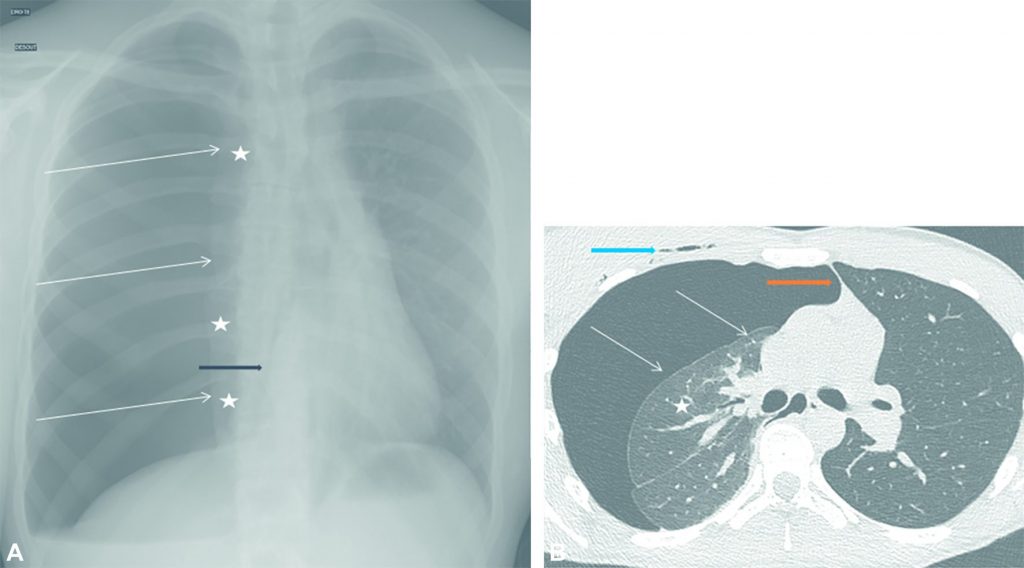

Un pneumothorax est la présence d’air dans l’espace pleural (cf. chapitre 98). Il se traduit par une hyperclarté périphérique avec visibilité de la plèvre viscérale. Le poumon a son contact est collabé et se voit sur la radiographie thoracique par une opacité plus ou moins importante en fonction du volume du pneumothorax (figure 100.1).

Fig. 100.1. Accident de la voie publique avec polytraumatisme.

(A) Radiographie de thorax de face. Ligne bordante axillaire (flèches blanches) avec zone claire avasculaire et poumon rétracté vers le hile (étoiles blanches) se compliquant d’une déviation médiastinale vers la gauche (la flèche noire montre le bord droit du cœur décalé vers la gauche) en rapport avec un pneumothorax complet compressif sur le médiastin. (B) Scanner thoracique en fenêtre parenchymateuse en coupe axiale. La plèvre viscérale (flèche blanche) est visible avec un poumon rétracté (étoile blanche) et une déviation médiastinale vers la gauche (flèche orange). Il existe de l’air sous-cutané appelé emphysème sous-cutané (flèche bleue) en rapport avec une fracture costale (non visible ici).

Source : CERF, CNEBMN, 2022.